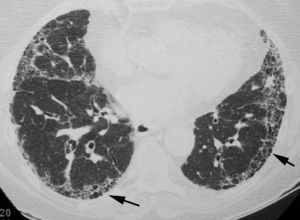

El objetivo es identificar los hallazgos típicos del patrón de NIU (fig. 3) y distinguirlos de los patrones menos específicos presentes en las otras neumonías intersticiales idiopáticas. Para evitar errores descriptivos y de concepto, la lectura radiológica debe utilizar una terminología descriptiva basada en la correlación radiológico-patológica, como la recomendada por la sociedad Fleischner22.

El consenso oficial ATS/ERS/JRS/ALAT 20112 establece que, en la TCAR, el diagnóstico de certeza de la NIU se basa en la identificación de los 4 hallazgos «típicos»: a)la afectación pulmonar debe tener un predominio basal y una localización subpleural; b)presencia de reticulación evidente; c)existencia de panalización con/sin bronquiectasias/bronquiolectasias de tracción, y d)demostrar la ausencia de hallazgos considerados excluyentes de un patrón de NIU (tabla 1, fig. 3). La presencia de vidrio deslustrado debe ser mínima o inexistente.

La panalización, formada por grupos de quistes con paredes finas, con una localización subpleural y un diámetro de entre 3 y 10mm, es un hallazgo imprescindible para diagnosticar con certeza el patrón de NIU. Cuando no hay panalización visible, el diagnóstico mediante la TCAR será el de posible patrón de NIU; en estos casos, el diagnóstico definitivo de NIU deberá realizarse mediante biopsia. La biopsia pulmonar puede evitarse únicamente cuando la TCAR muestre un patrón de certeza típico de NIU. El valor predictivo positivo de la TCAR en el diagnóstico de la NIU es del 90 al 100%. Un patrón de NIU puede identificarse también en la neumonitis por hipersensibilidad crónica, la asbestosis y algunas conectivopatías23.